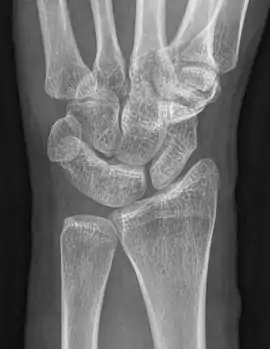

Carpal coalition

An example of a lunotriquetral coalition, the most commonly fused carpal bones

Carpal coalition is the abnormal fusion of two or more carpal bones when they fail to segment during intrauterine development.[1] First described by Eduard Sandifort in 1779, carpal coalitions are often an isolated issue which connect two carpal bones in the same row of the wrist.[2] These issues are congenital and occur at various rates throughout the population.[3]

The lunate and triquetral bones are the most common carpal bones to fuse together, resulting in a lunotriquetral coalition in 1% of people. 60% of patients with a lunotriquetral coalition will have it bilaterally.[1] Among isolated incidents the capitate and hamate bones are the next most common to fuse followed by the pisiform-triquetrum, trapezium-trapezoid, scaphoid-capitate, and triquetrum-hamate.[3]